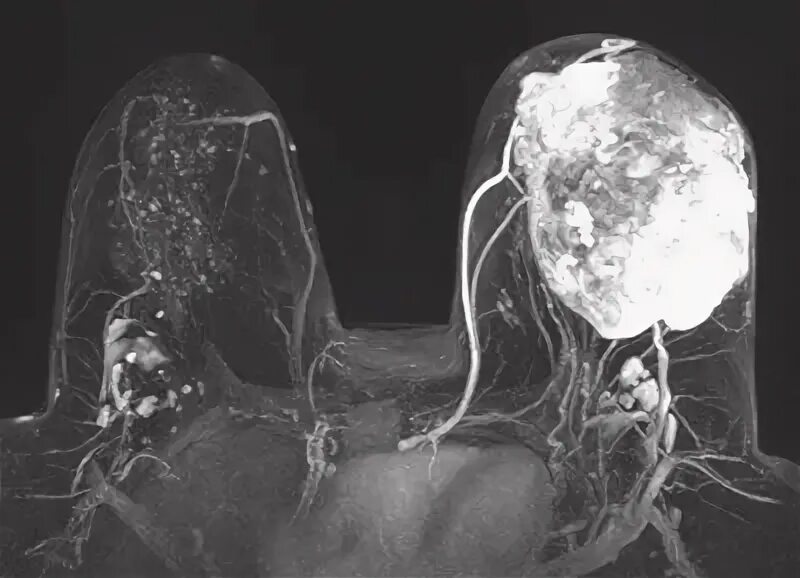

Мрт молочных желез